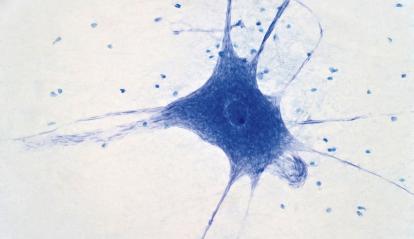

La immunologia és una branca del coneixement que estudia el sistema immunitari i el seu funcionament analitzant com identifica el cos les cèl·lules pròpies, detecta els potencials «enemics» externs i activa mecanismes de defensa per mantenir-los sota control. Gràcies a aquest coneixement s’han assolit fites tan fonamentals com el desenvolupament de vacunes eficients i l’erradicació de la verola, un dels avenços més grans de la medicina moderna.

Així mateix, també estudia com aquesta maquinària ens protegeix davant d’amenaces internes, com ara les cèl·lules canceroses, i també els sofisticats mecanismes de control que necessita per aturar-se i no danyar els nostres teixits. Més recentment, a través de l’anomenada immunoteràpia, la comunitat científica està aprenent a reprogramar les cèl·lules immunitàries amb l’objectiu de modificar les cèl·lules del mateix pacient perquè actuïn de manera terapèutica.